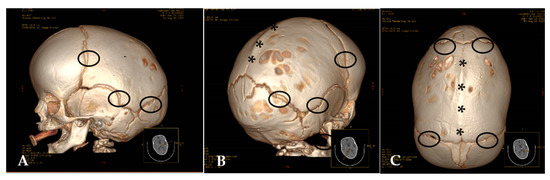

- Marsh, J.L.; Vannier, M.W. The “third” dimension in craniofacial surgery. Plast. Reconstr. Surg. 1983, 71, 759–767. [Google Scholar] [CrossRef] [PubMed]

- Vannier, M.W.; Marsh, J.L.; Warren, J.O. Three dimensional CT reconstruction images for craniofacial surgical planning and evaluation. Radiology 1984, 150, 179–184. [Google Scholar] [CrossRef] [PubMed]

- Parisi, M.; Mehdizadeh, H.M.; Hunter, J.C.; Finch, I.J. Evaluation of craniosynostosis with three-dimensional CT imaging. J. Comput. Assist. Tomogr. 1989, 13, 1006–1012. [Google Scholar] [CrossRef] [PubMed]

- Kirmi, O.; Lo, S.J.; Johnson, D.; Anslow, P. Craniosynostosis: A radiological and surgical perspective. Semin. Ultrasound CT MRI 2009, 30, 492–512. [Google Scholar] [CrossRef] [PubMed]

- Kotrikova, B.; Krempien, R.; Freier, K.; Mühling, J. Diagnostic imaging in the management of craniosynostoses. Eur. Radiol. 2007, 17, 1968–1978. [Google Scholar] [CrossRef] [PubMed]